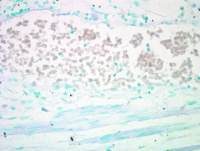

ICC/IF analysis of HUVEC cell treated with 100ng of VEGF for 30 minutes using GTX25473 VEGF Receptor 2 (phospho Tyr1054/Tyr1059) antibody. Panel e is untreated cell with no signal. Panel f represents control cells with no primary antibody to assess background.

Green : Primary antibody

Blue : Nuclei

Red : Actin

Fixation : 4% PFA

Permeabilization : 0.1% Triton X-100 for 10 minutes